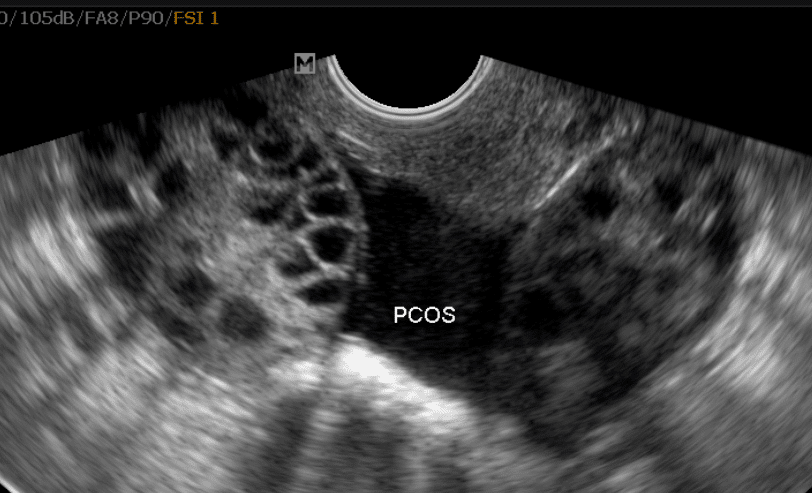

In this episode we finish up PCOS by discussing the management and long-term consequences.